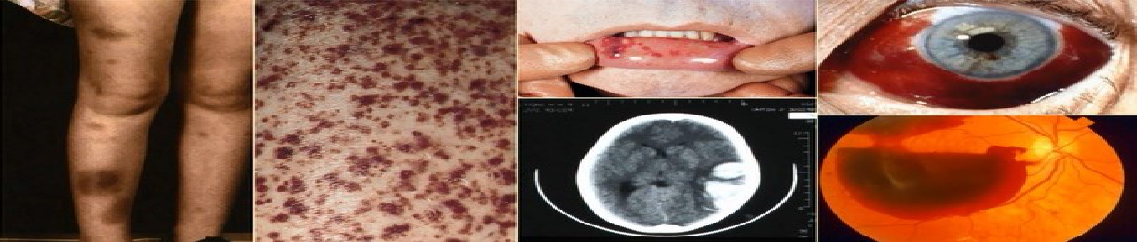

原发免疫性血小板减少症(primary immune thrombocytopenia,ITP),既 往称特发性血小板减少性紫癜,是一种获得性自身免疫性出血性疾病。 该病的发生是由于患者对自身血小板抗原的免疫失耐受,产生体液免疫和细胞免疫介导的血小板过度破坏和血小 板生成受抑,出现血小板减少,伴或不伴皮肤黏膜出血的临床表现。

2.出血倾向